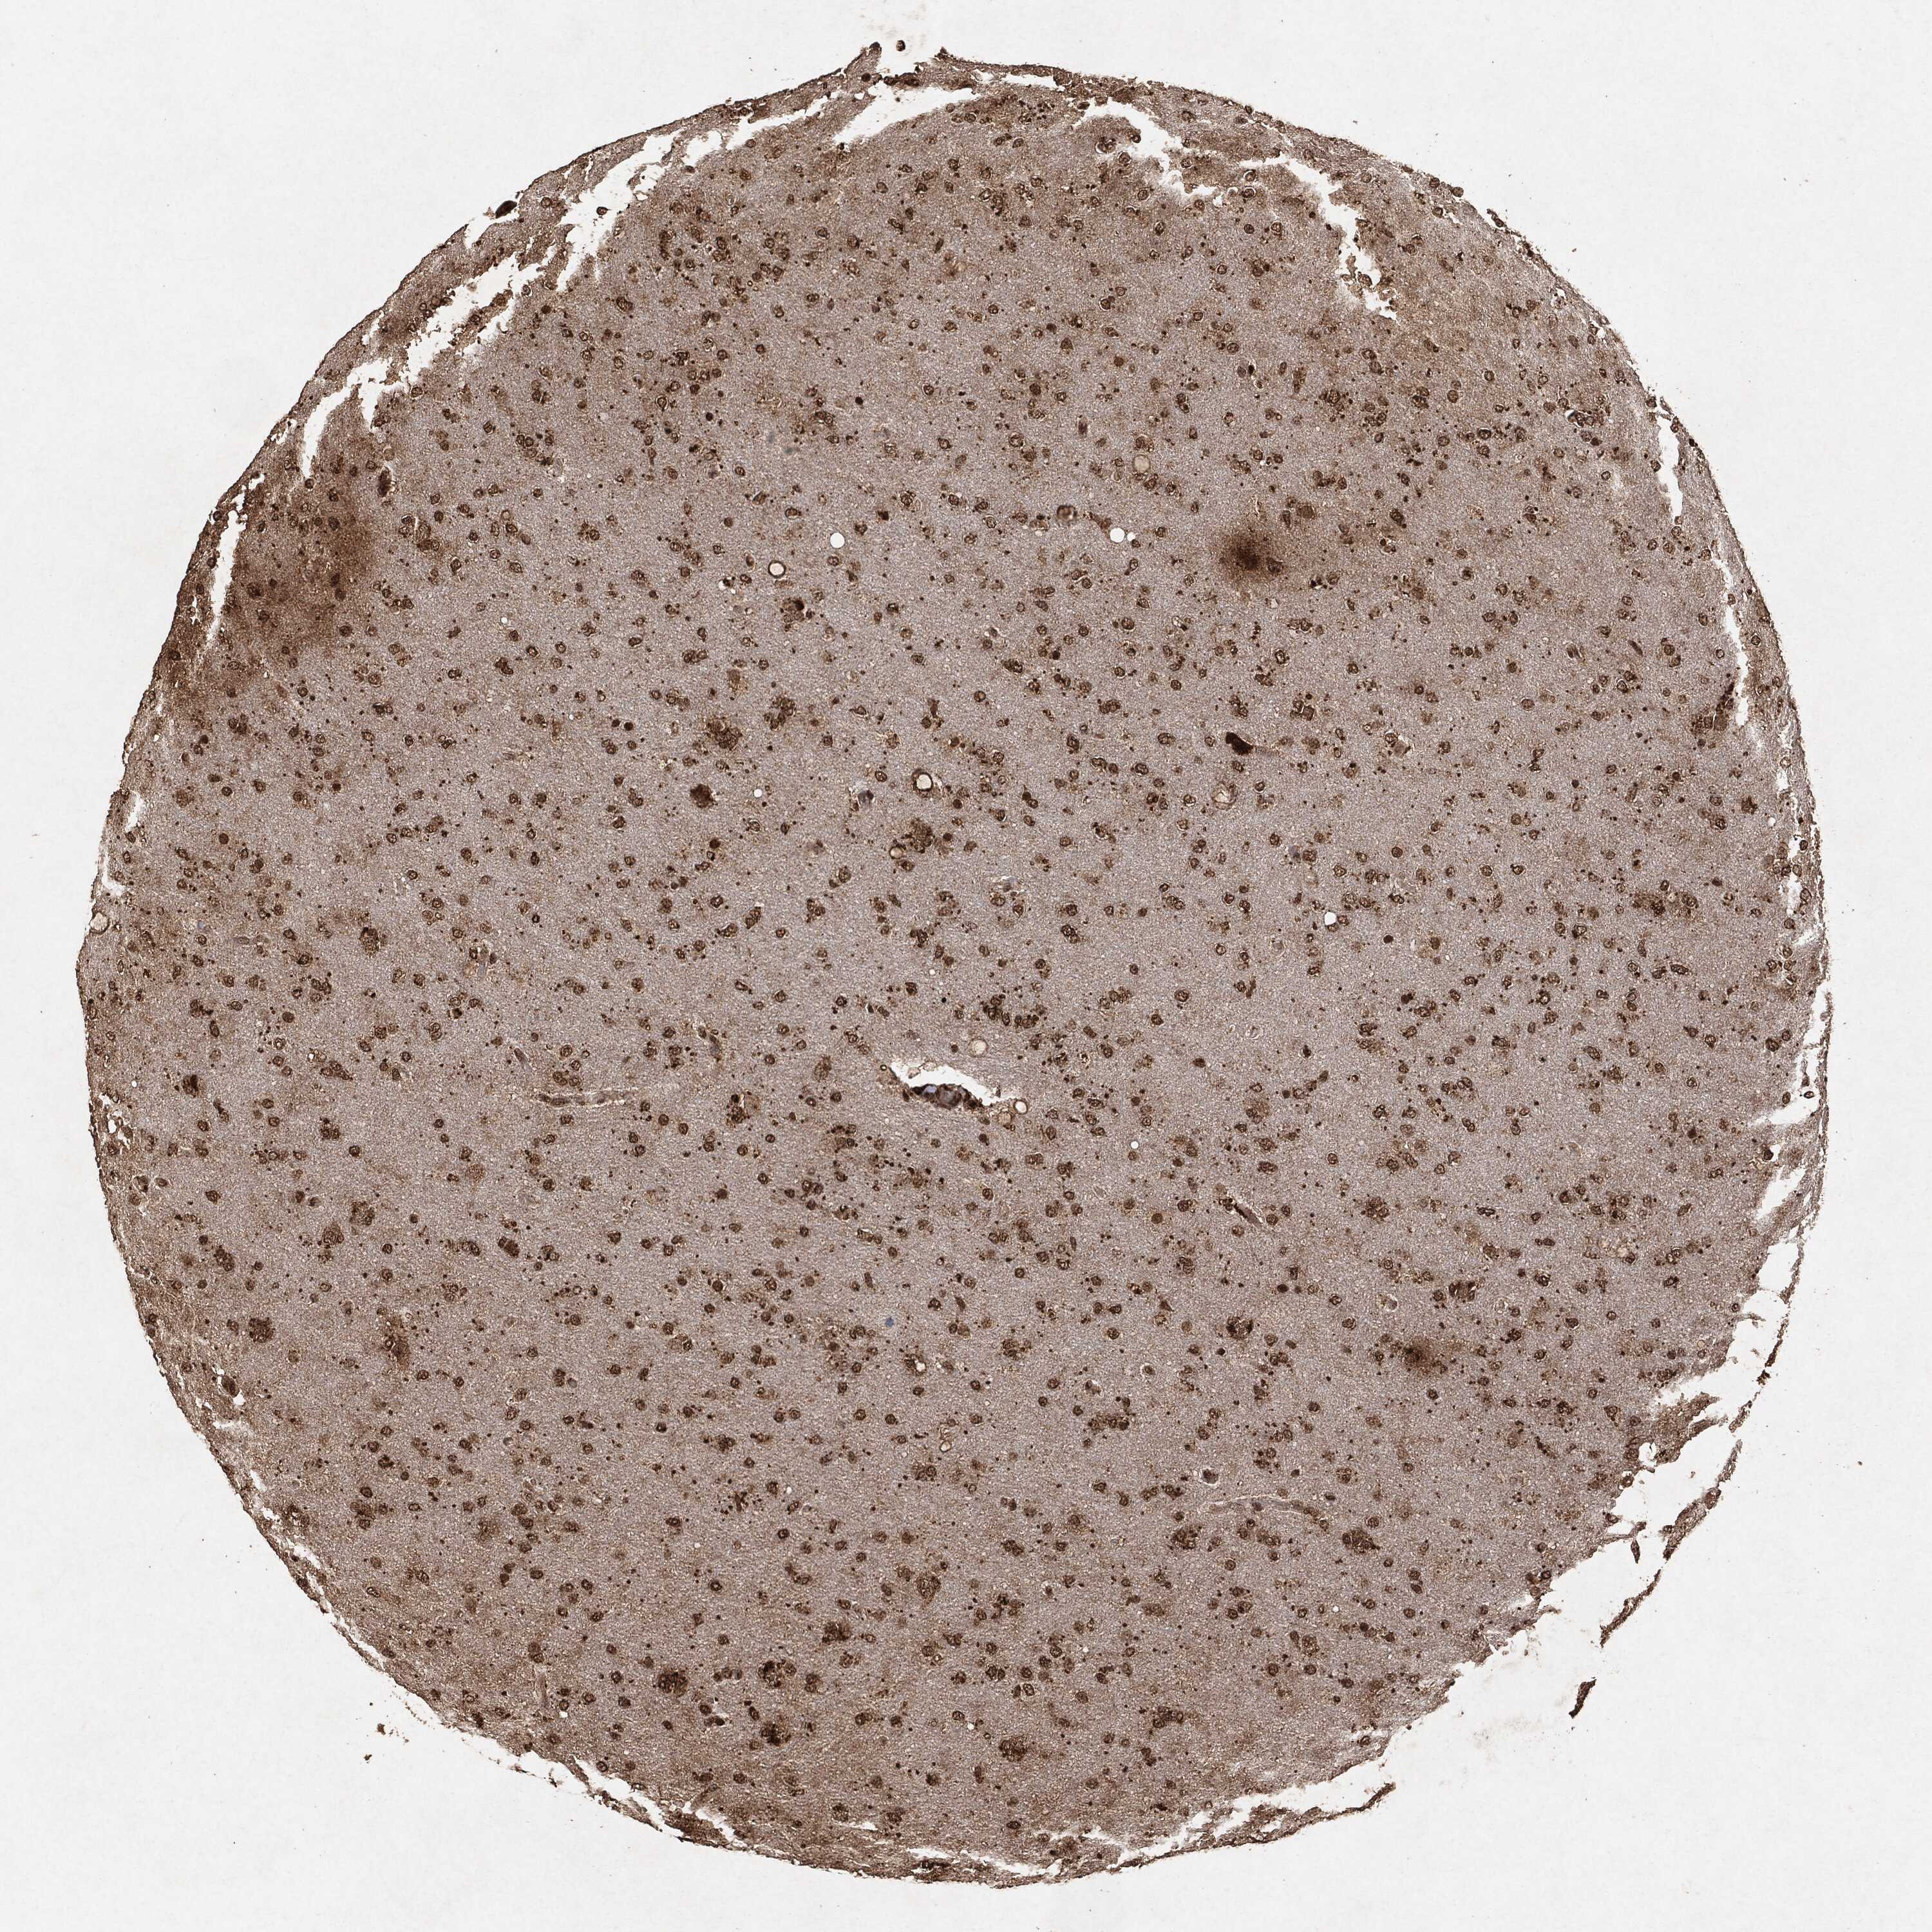

GLIOMA - Protein expressioni

A mouse-over function shows sample information and annotation data. Click on an image to view it in a full screen mode. Samples can be filtered based on level of antibody staining by selecting one or several of the following categories: high, medium, low and not detected. The assay and annotation is described here.

Note that samples used for immunohistochemistry by the Human Protein Atlas do not correspond to samples in the TCGA dataset.

Antibody stainingi

Antibody staining in the annotated cell types in the current human tissue is reported as not detected, low, medium, or high, based on conventional immunohistochemistry profiling in selected tissues. This score is based on the combination of the staining intensity and fraction of stained cells.

Each image is clickable and will lead to virtual microscopy that enables deeper exploration of all samples and also displays staining intensity scores, fraction scores and subcellular localization as well as patient and tissue information for each sample.

Glioma, malignant, High grade

Glioma, malignant, Low grade

Glioma, malignant, NOS